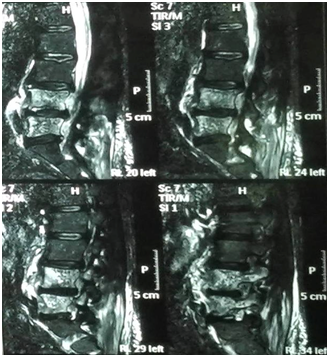

As patient still having backache, Magnetic Resonance Imaging (MRI) lumbo-sacral region was done to evaluate any deterioration in the disc prolapse state. Paraspinal mass was illustrated in MRI assessment (Figure 1) suggestive of metastatic lesion. So, bone scan was ordered to evaluate the nature of the lesion, and the results revealed neoplastic lesion involving L4 (Figure 2).

Figure 1 Non contrast MRI lumbosacral spine, bone marrow of L4 and L5 is seen replaced by abnormal SI in form of low SI on T1 and high SI on both T2 and STIR images?? Mostly metastatic lesion.

This what exactly happened to our case with normalization of liver function tests by proper treatment of her sepsis. Imaging studies including plain x-ray and CT could be useful. However, MRI is the most sensitive, radioisotope is a helpful adjunct, and biopsy (either percutaneous needle or open surgical) is generally needed to confirm the clinical and/or radiographic suspicion. Samples should be sent for aerobic, anaerobic, mycobacterial and fungal culture and pathology.

In our case, MRI suggested metastatic bone lesion which was changed to a diagnosis of paraspinal abscess on surgery indicating the mandatory need for confirmation of the diagnosis through biopsy. Surgical drainage of the paraspinal abscess under coverage of systemic antibiotic was the treatment of choice in this case as reported in literature.13